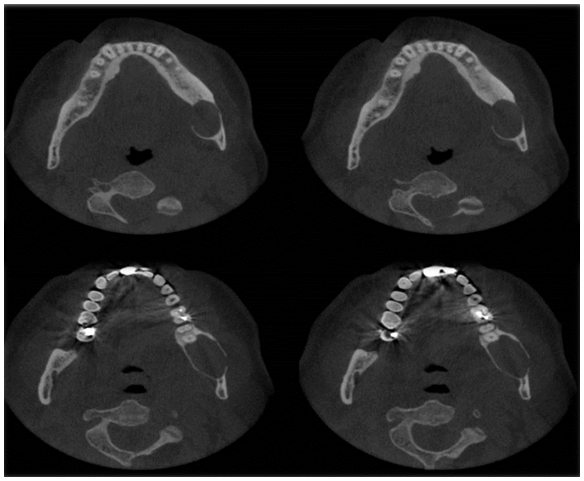

A CBCT was performed to identify the extension of the lesion and its relation with the IAC. Panoramic reconstruction (Figure 2A & 2B) shows a well-defined low density unilocular lesion circumscribing the crown of tooth #38 located vertically from the mid ramus extending below the level of the IAC, horizontally it extend from the apical third of the mesial root of #37 till the mid portion of the ascending ramus. Axial cuts (Figure 3) show expansion of the alveolar process and thinning and interruption of both lingual and buccal cortical plates. The roots of #37 show no resorption. The lesion is attached to tooth #38 at the level of the CEJ (Figure 4). The ectopic position of the IAC is also seen very clearly in the maximum intensity projection panoramic reconstruction (Figure 2B) and in the cross sectional images which shows the canal within the lesion (Figure 5A & 5B). After clinical and radiographic examination, a provisional diagnosis of dentigerous cyst was made; however, kerato cyst odontogenic tumor, amleloblastoma, ameloblastic fibroma were also considered in the differential diagnosis. Keratocyst don’t expand the bone to the same degree as presented here and attachment to the teeth will be more apically. Ameloblastic fibroma usually occurs in young patients which is not the case. Ameloblastoma would have presented internal septa if big in size as in this case. The most probable diagnosis is dentigerous cyst. The operation was performed under local anesthesia. Incision was made followed by raising a full thickness buccal mucoperiosteal flap. The lesion was then identified and the canal was viewed and confirmed, as seen on CBCT, to be passing in the center of the lesion. Dissection of the lesion away from the canal was performed using a tissue holder. With proper identification and isolation, the inferior nerve was preserved and the cyst was totally enucleated. Tooth number #38 was removed, and preservation of tooth #37. No sign of paresthesia was recorded after surgery. The surgical specimen was then sent for pathological analysis for final diagnosis. The histological examination showed a cystic lumen with blood content, a very thin lining of non-keratinized stratified squamous epithelium and dense fibro cellular connective tissue stroma with chronic inflammatory infiltrate. A macrophage and giant cell granuloma is noted around cholesterol crystals. There is no evidence of malignant change. The cyst opened measured 4x2x1 cm. A chronic inflamed dentigerous cyst was confirmed. Follow up CBCT was done after 3years of the surgery, and a progressive improvement in bone regeneration and healing process at the site of surgery was observed (Figure 6A & 6B); vitality test on tooth #37 response was positive.

Figure 2A Panoramic reconstruction showing the ectopic position of the IAC.

Figure 2B Maximum intensity projection confirming the IAC position.

Figure 3 Axial cuts (1.2 mm interval) at the level of mid root showing of both lingual and buccal cortical plates and interruption of the buccal lingual cortical plates at different levels; marked expansion of the cortical plate is also noted.